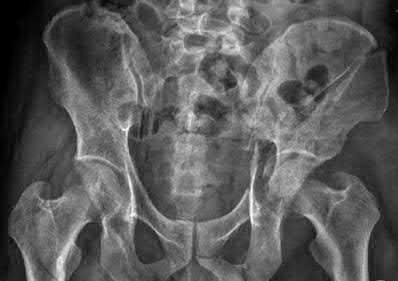

Question 11:

A poly-trauma patient presents hemodynamically unstable with an anteroposterior compression (APC-III) pelvic ring injury. A circumferential pelvic binder is requested to reduce pelvic volume and control hemorrhage. To be anatomically effective, the binder must be centered precisely over which of the following landmarks?

Options:

- Iliac crests

- Anterior superior iliac spines

- Greater trochanters

- Ischial tuberosities

- Symphysis pubis

Correct Answer: Greater trochanters

Explanation:

For optimal mechanical advantage and effective reduction of an 'open book' pelvic fracture (APC type), a pelvic binder must be applied directly over the greater trochanters of the femurs. Applying it higher, such as over the iliac crests, is a common error that fails to adequately close the pelvic ring and can paradoxically open the true pelvis.